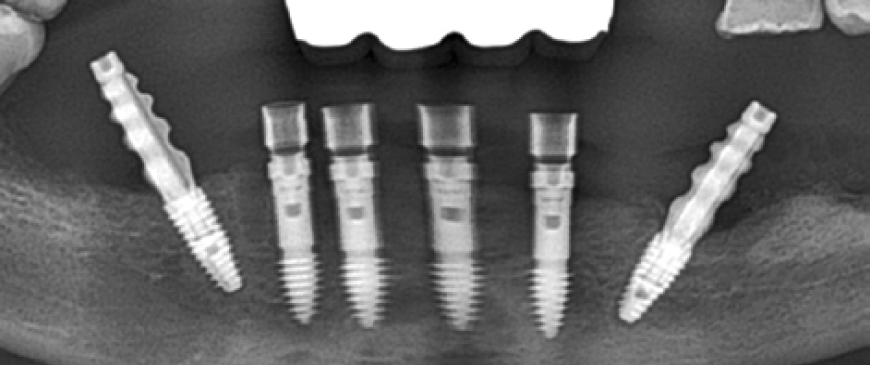

Fig 8

Post-surgery panoramic radiograph. Immediately after the surgery, impressions were taken to prepare provisional prostheses.

Fig 11

Panoramic image when custom abutments and PMMA bridge were placed.